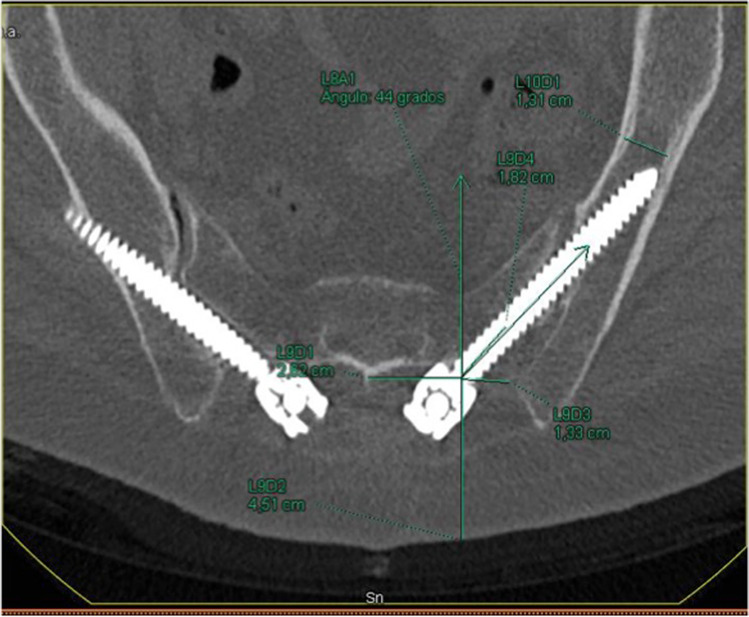

In order to determine which technique correlates better with the ideal trajectories, the percentage of difference between ideal and real trajectories for each technique was calculated parameter by parameter, awarding 100% to the ideal trajectory. Hereafter, differences between groups were analyzed by comparing the mean and the standard deviations of each parameter. As shown in Table 3, the AI technique adapts better to the morphological features of the pelvic in all parameters, except for the sagittal plane angulation (p = 0.832), skin distance (p = 0.497), and iliac width (p = 0.233), where no statistical differences were found between both techniques (Fig. 3).

Fig. 3.

Bilateral S2AI screws. The right screw is not well oriented and breaks the cortical wall. On the left side, even though it is correctly oriented, it cannot go through the iliac isthmus

In terms of complications, there were no cases of vascular or neurologic complications, implant prominence, anchor migration, pseudarthrosis, or iliac pain. Ten cases of external cortical wall breakage were reported in S2AI group (Fig. 4), whereas only 4 were observed in the AI group (p = 0.047). There were no cases of medial cortical wall breakage or radiculopathy in S2AI group compared with 1 instance each found in the AI group (one patient with a lumbar construction extended to the pelvis with postoperative radiculalgia unrelated to the iliac screw that improved after a short course of oral steroids).